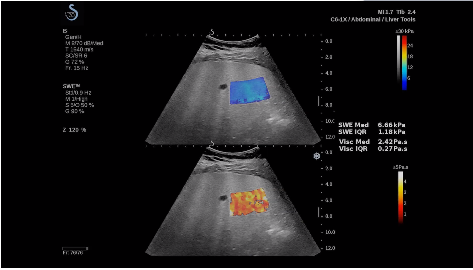

法國(guó)聲科影像(SuperSonic Imagine,SSI. Euroniex:FR0010526814)近日發(fā)表公告,宣布其研發(fā)的新一代“極速”超聲成像平臺(tái)(UltraFast Imaging),首次實(shí)現(xiàn)了肝臟的多項(xiàng)超聲定量評(píng)估新指標(biāo)同步檢測(cè),包括:Att PLUS,SSp PLUS和Vi PLUS等,基本涵蓋肝臟相關(guān)病理變化指征的如纖維化、脂肪變、炎癥等。據(jù)悉,此多項(xiàng)新技術(shù)新將搭載于新Aixplorer系列E超系統(tǒng)。

E超相關(guān)技術(shù)已被多項(xiàng)多中心大樣本研究證實(shí)對(duì)于肝纖維化無(wú)創(chuàng)評(píng)估有重要意義,同時(shí)也可全面應(yīng)用于乳腺、甲狀腺、肝臟、前列腺、肌骨、婦科等全身各組織器官的定量評(píng)估和鑒別診斷。在慢性肝臟方面,聲科E超的肝臟相關(guān)定量診斷技術(shù)集,于2018年獲得美國(guó)FDA認(rèn)證,成為FDA歷史上首次獲批的單病種超聲全面定量解決方案。

E超是在原有B超、彩超(彩色多普勒CDFI)基礎(chǔ)上研發(fā)成功的新一代超聲剪切波彈性成像系統(tǒng),是一種能夠全面應(yīng)用于表淺組織、腹部臟器,血管等方面的組織彈性成像技術(shù)。根據(jù)組織硬度彈性值的不同,有效鑒別實(shí)性腫瘤的良惡性。對(duì)于惡性病變的診斷具有較高的特異性和敏感性,尤其對(duì)于甲狀腺、乳腺、前列腺等小器官,能夠完成常規(guī)超聲不能完成的組織定量分析,可以實(shí)時(shí)、全幅、全定量獲得組織彈性(硬度)信息,為鑒別腫瘤的良惡性提供客觀、量化的診斷依據(jù)。